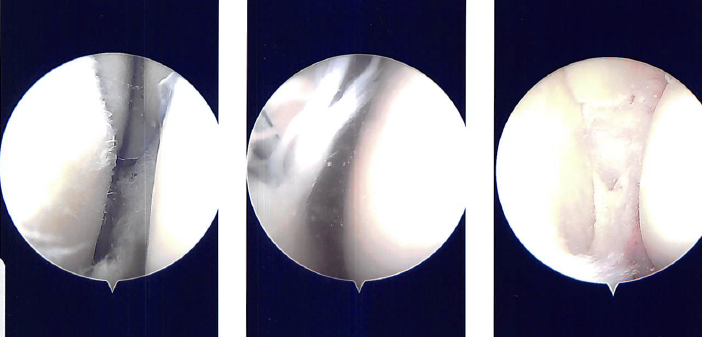

A lateral incision for the entry portal was created near the patella. The scope was given. The medial meniscus tear was visible after the scope was transferred from the patellofemoral joint to the medial compartment. The lateral compartment was examined with the scope, and it revealed fraying of the lateral meniscus and a tear in its anterior horn.

Making a medial entry portal with a spinal needle allowed for easier access to the medial and lateral compartments. A portal for entry was then created. Introduced to do the synovectomy was Shaver.

The complicated tear of the posterior horn and body of the medial meniscus was removed using upbitters and straight biters during the medial meniscectomy. Shaver was used to empty the parameniscal cyst and debride and transect margins.

The knee was discovered to be intact when the scope was advanced to the intercondylar region. The lateral compartment received the scope. The anterior horn of the lateral meniscus was torn, and the medial edge of the lateral meniscus was frayed. The meniscus was cleaned off using a razor.

There were margins of balance. Final images were captured and stored. On the medial and lateral femoral condyles, there was no arthritis. There was grade 1 to grade 2 arthritis on the lateral tibial plateau.

The scope was moved to the patellofemoral joint where no arthritis was found over the patella as well as the trochlea. Final pictures were taken and saved. The knee was thoroughly lavage.